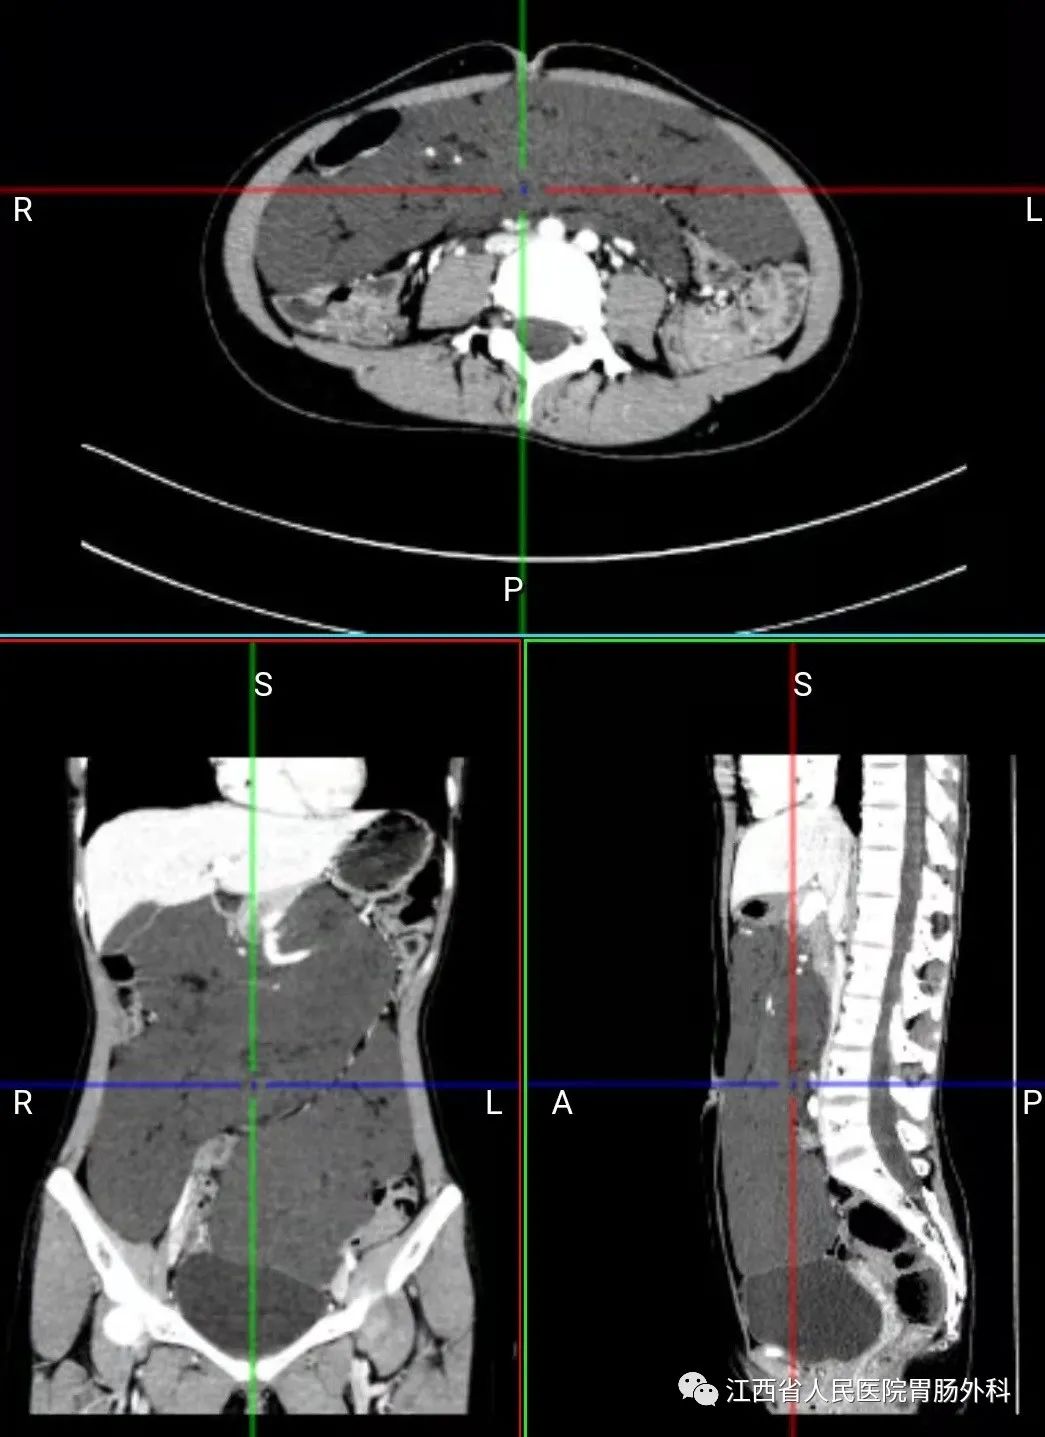

入院后完善相关检查,腹部CT显示:腹、盆腔巨大占位。PET-CT也提示恶性肿瘤的可能性,肿瘤是良性还是恶性?能不能完全切除?切除后有哪些并发症和后遗症?问题一个又一个,小洁及家属忧心如焚。

经各位专家讨论:①腹腔肿瘤非常之大,最大横切面达到8.7*19.7cm,充满整个腹腔,包绕肠系膜上血管及其分支,需要在不损伤大血管的前提下切除肿瘤,并尽量保留肠管血供,手术难度非常大,风险很高;②目前不能排除恶性肿瘤的可能,如为恶性肿瘤,则预后很差,手术后生存期不长,且生活质量差;③双侧肾积水考虑为肿瘤压迫所致;④妇科会诊后暂不考虑卵巢来源肿瘤,如果术中有需要,妇科团队可以随时支援。